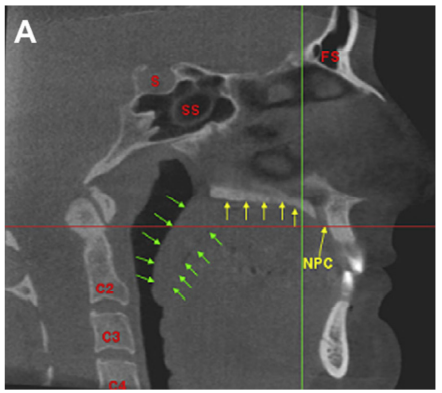

Arrows - eustachian tube